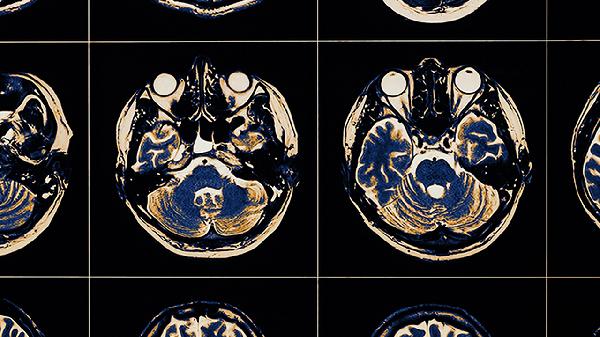

脑血栓中风后遗症患者需保持低盐低脂饮食,每日摄入优质蛋白如鱼肉、豆制品。家属应协助进行被动关节活动,预防肌肉挛缩和深静脉血栓。定期复查头颅CT评估恢复情况,出现新发症状需及时就医。建立规律作息,避免情绪激动和过度劳累。